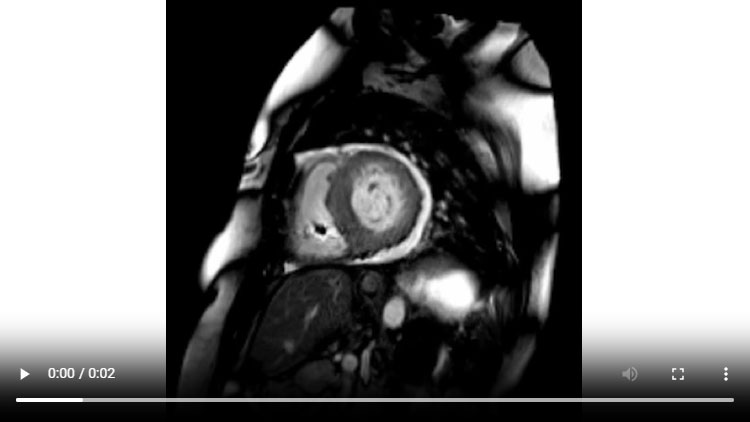

Figure 1A : Séquence Ciné-IRM - Coupes petit-axe basal

- Présence d’une hypertrophie ventriculaire gauche (HVG) asymétrique à prédominance septale mesurée au maximum à 23 mm.

- Visualisation de la sonde de PM avec artéfacts métalliques modérés au niveau du ventricule droit (flèches roses).

- Présence d’un épanchement péricardique de moyenne abondance (flèches rouges).